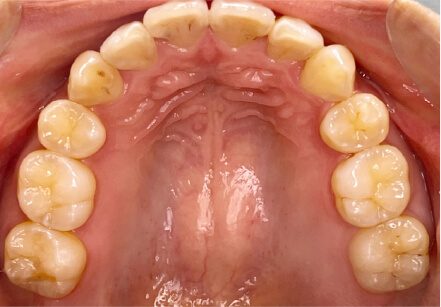

叢生の症例

10歳

/

女性

相談内容

スペース不足

カウンセリング・診断結果

myoからの移行。スペース不足のためインビザライン開始。

治療内容・方法

全額アライナー矯正

術後の経過・現在の様子

クリアライナー使用

治療のリスク

痛み・歯根吸収・歯肉退縮・虫歯・後戻り

費用・治療期間

(インビザのみ)385,000円、1年2ヶ月 + myo3年4ヶ月

トレーニングなど